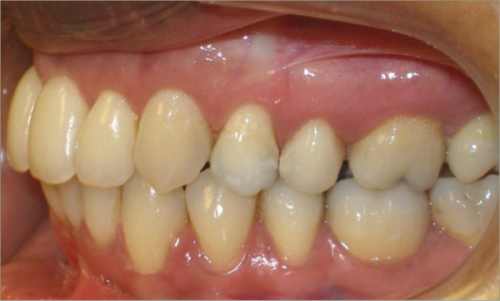

32 year old female:

Diagnosis:

- Previously lost upper first molars

- Severe lower arch crowding

- Midline discrepancy

- Narrow upper arch form

Treatment:

- Extraction of lower right first bicuspid

- Substitution of upper second molars for first molars

- Full fixed appliances

- 23 months